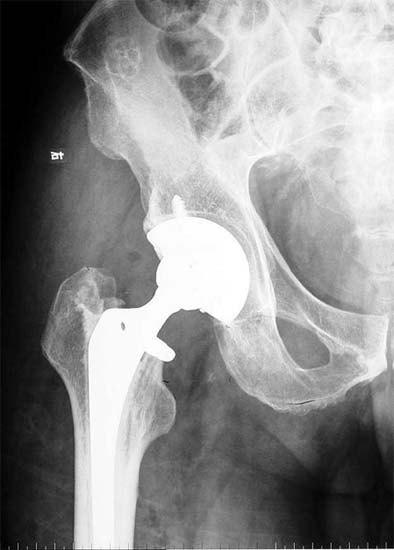

骨性关节炎关节软骨破坏,股骨头坏死 股骨颈骨折,容易发生不愈合

切除病变的股骨头,全髋置换